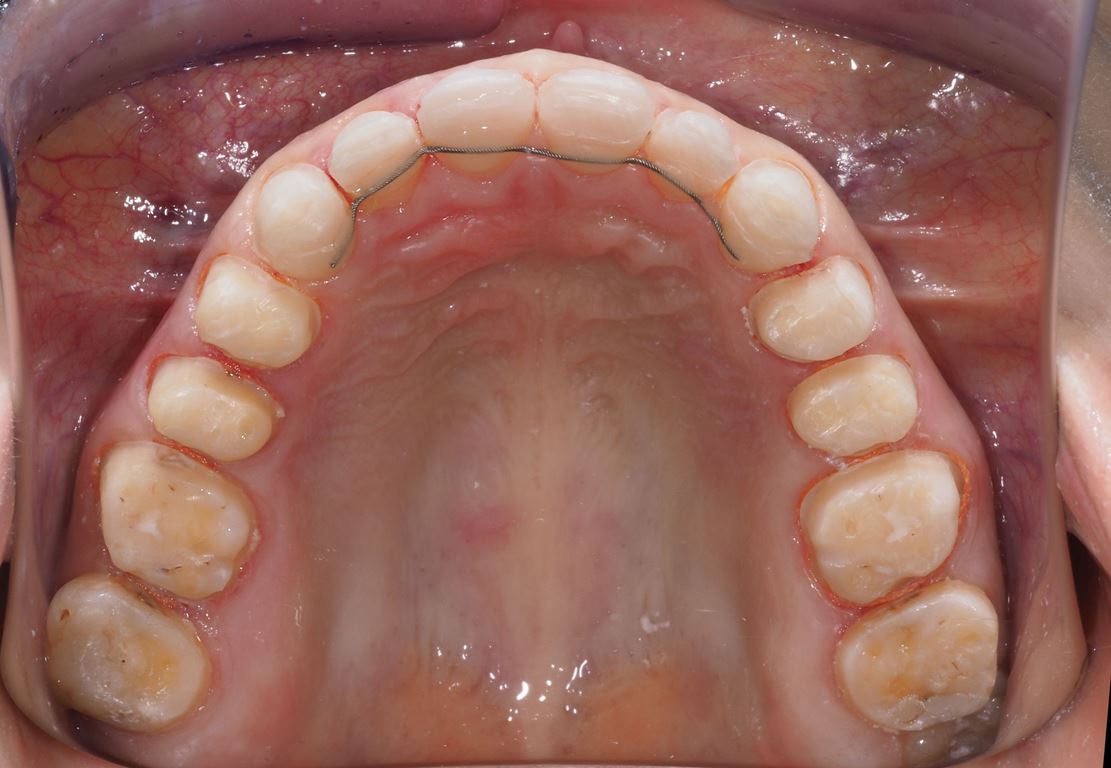

Bezpośrednio po usunięciu zębów rozpoczęto leczenie ortodontyczne, które trwało 15 miesięcy i pozwoliło na uzyskanie zaplanowanych wcześniej pozycji zębów (ryc. 22-24).

Następnie, po okresie stabilizacji i wstępnej korekcie okluzji, na podstawie analizy nowego kompletu zdjęć i modeli, wykonano woskowanie diagnostyczne oraz mock-up górnego łuku zębowego mający na celu potwierdzenie ostatecznego kształtu zębów i zakresu niezbędnego przygotowania chirurgicznego (ryc. 25-27).

Następny etap leczenia polegał na adhezyjnym osadzeniu rekonstrukcji wykonanych z materiału E-max (Ivoclar, Liechtenstein). Po cementowaniu przystąpiono do preparacji zębów dolnego łuku zębowego. Pozostawienie wszystkich drugich zębów trzonowych w pierwotnym kształcie umożliwiło łatwą rejestrację pozycji żuchwy w RC przed rozpoczęciem preparacji, którą wykonano na twardym materiale (LuxaBite, DMG, Niemcy) (ryc. 32, 33). Po zakończeniu preparacji rejestrat zwarciowy powiększono o odcinek przedni, wykonano wyciski oraz zabezpieczono filary wcześniej przygotowanymi i podścielonymi uzupełnieniami z PMMA (ryc. 34-36). Podobnie jak w łuku górnym, w następnym etapie sprawdzono wewnątrzustnie prototyp rekonstrukcji wyfrezowany w PMMA, na którym wykonano niezbędne korekty zwarcia (ryc. 37, 38). Ostatni etap leczenia polegał na adhezyjnym cementowaniu rekonstrukcji dolnego łuku zębowego.